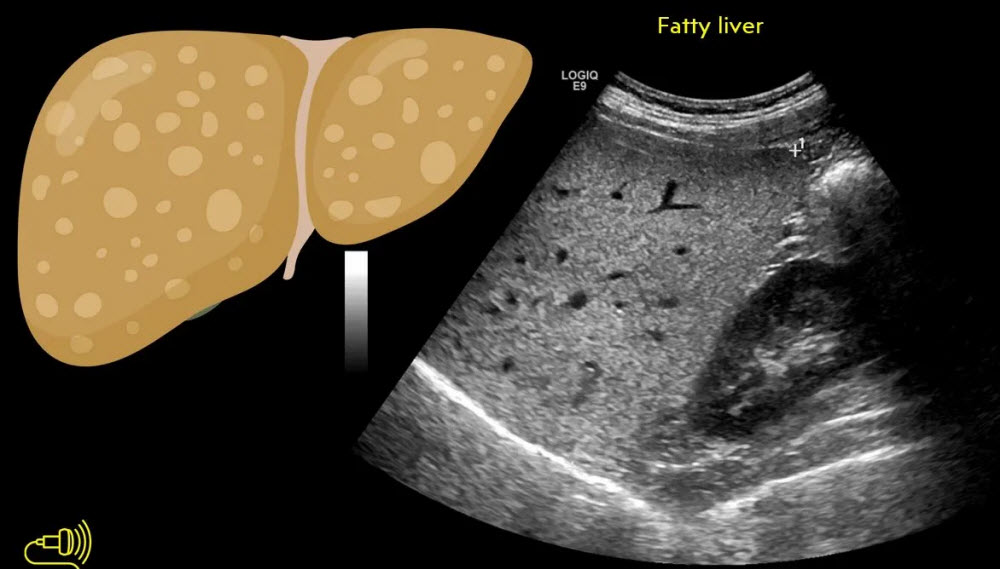

• کبد چرب: رسوب چربی در سلولهای کبدی که میتواند منجر به مشکلات جدی شود با سونـوگرافی قابل تشخیص است.